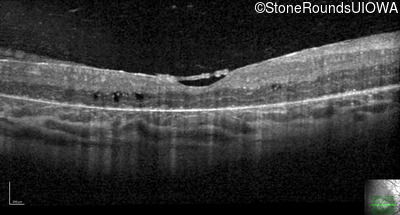

Optical Coherence Tomography - Right - 20/160

Exemplar / OCT Stack

OCT Stack